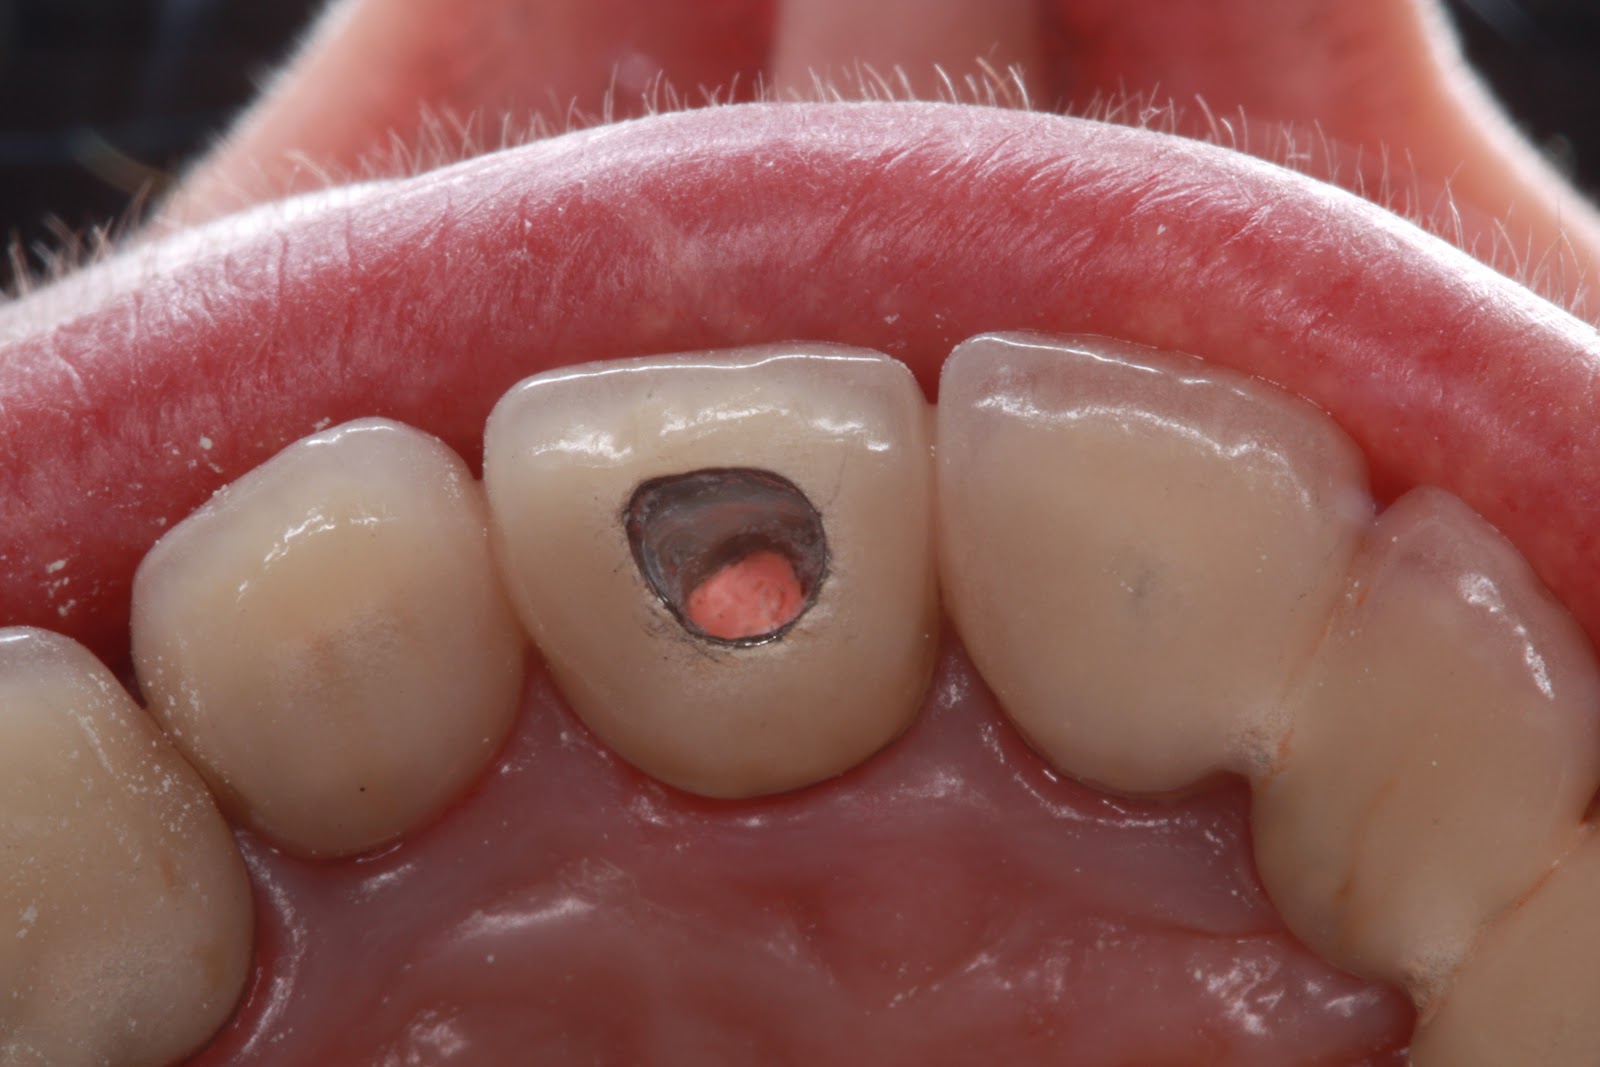

Οι οδοντικές κοιλότητες (τρύπες) σχηματίζονται στα δύο εξωτερικά στρώματα ενός δοντιού, το σμάλτο και την οδοντίνη. Το σμάλτο είναι η εξωτερική, λευκή, σκληρή επιφάνεια και η οδοντίνη είναι το κίτρινο στρώμα ακριβώς κάτω από το σμάλτο. Και τα δύο στρώματα χρησιμεύουν για την προστασία του εσωτερικού ιστού, που ονομάζεται “πολτός του δοντιού” (pulp), όπου βρίσκονται τα αιμοφόρα αγγεία και τα νεύρα.

Οι τρύπες στα δόντια είναι κοινές, επηρεάζοντας πάνω από το 90% του πληθυσμού. Οι μικρές κοιλότητες μπορεί να μην προκαλέσουν πόνο και μπορεί να παραμείνουν απαρατήρητες από τον ασθενή. Οι μεγαλύτερες κοιλότητες μπορεί να συλλέγουν τροφές και ο εσωτερικός πολτός μπορεί να ερεθιστεί από βακτηριακές τοξίνες, τροφές που είναι κρύες, ζεστές, ξινές, ή γλυκές και να προκαλέσει έντονο πονόδοντο.

Οι τροφές που μένουν στο στόμα και δεν απομακρύνονται με το βούρτσισμα, αποσυντίθενται και δημιουργούν βακτήρια που τρέφονται από απλά σάκχαρα. Αυτά τα βακτήρια δημιουργούν και την πλάκα στα δόντια, η οποία είναι όξινη και καταστρέφει σταδιακά το σμάλτο και την οδοντίνη. Εν τέλει, μαλακώνουν τόσο πολύ το σμάλτο που το σάλιο το διαβρώνει εντελώς και ανοίγει η τρύπα.

Από εκεί και πέρα ξεκινάει η σταδιακή διάβρωση του δοντιού, η τρύπα μεγαλώνει συνεχώς, μέχρι που τα βακτήρια βρίσκουν δίοδο στον “πολτό” και δημιουργείται απόστημα.